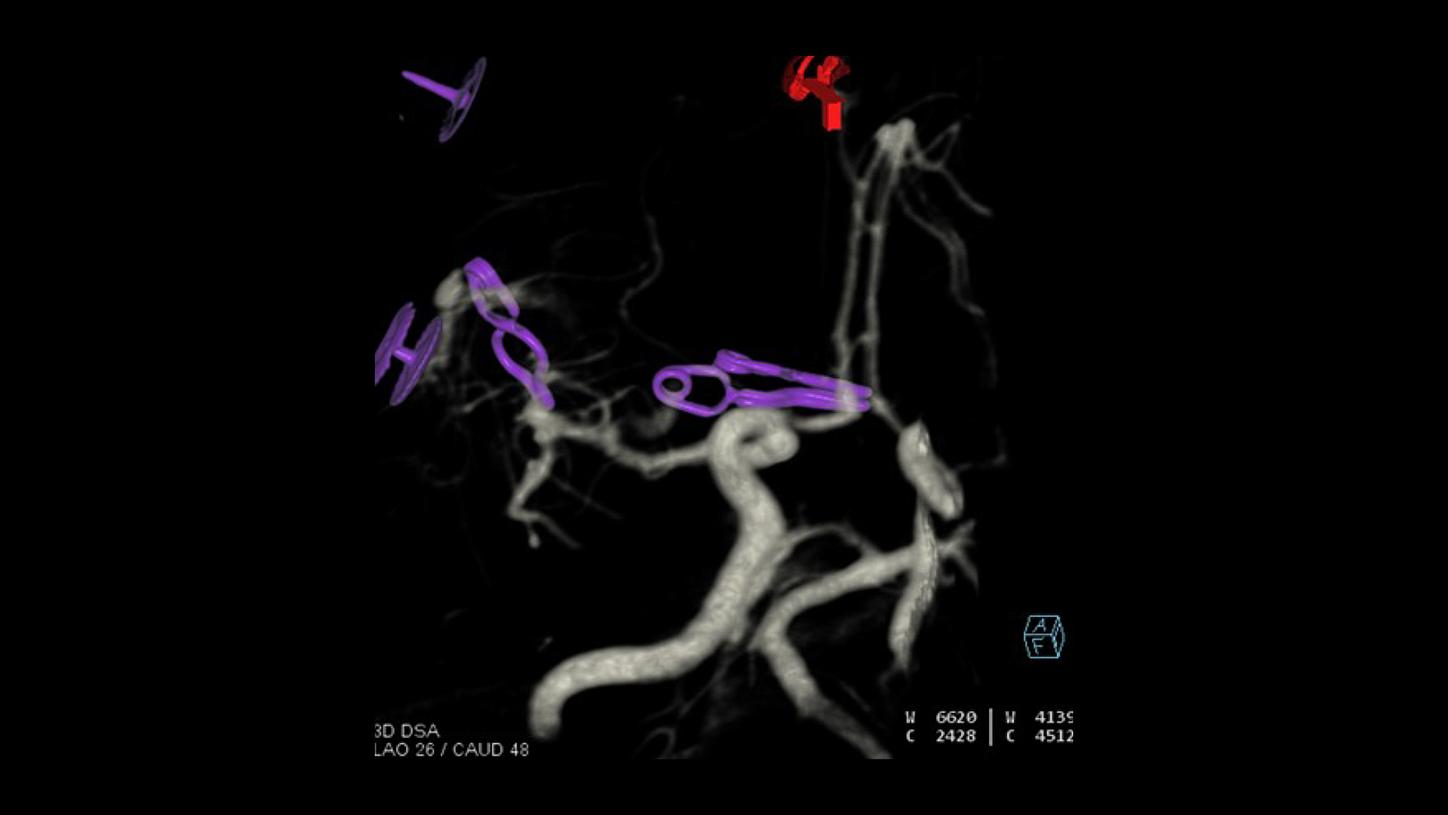

AP projection

Lateral projectionFollow-up DSA to visualize treatment success

- Follow-up syngo DynaCT after clipping, with intravenous contrast media injection

- Axial maximum intensity projection of the clipped aneurysm

- Dual-volume vessel presentation of the clipped aneurysm